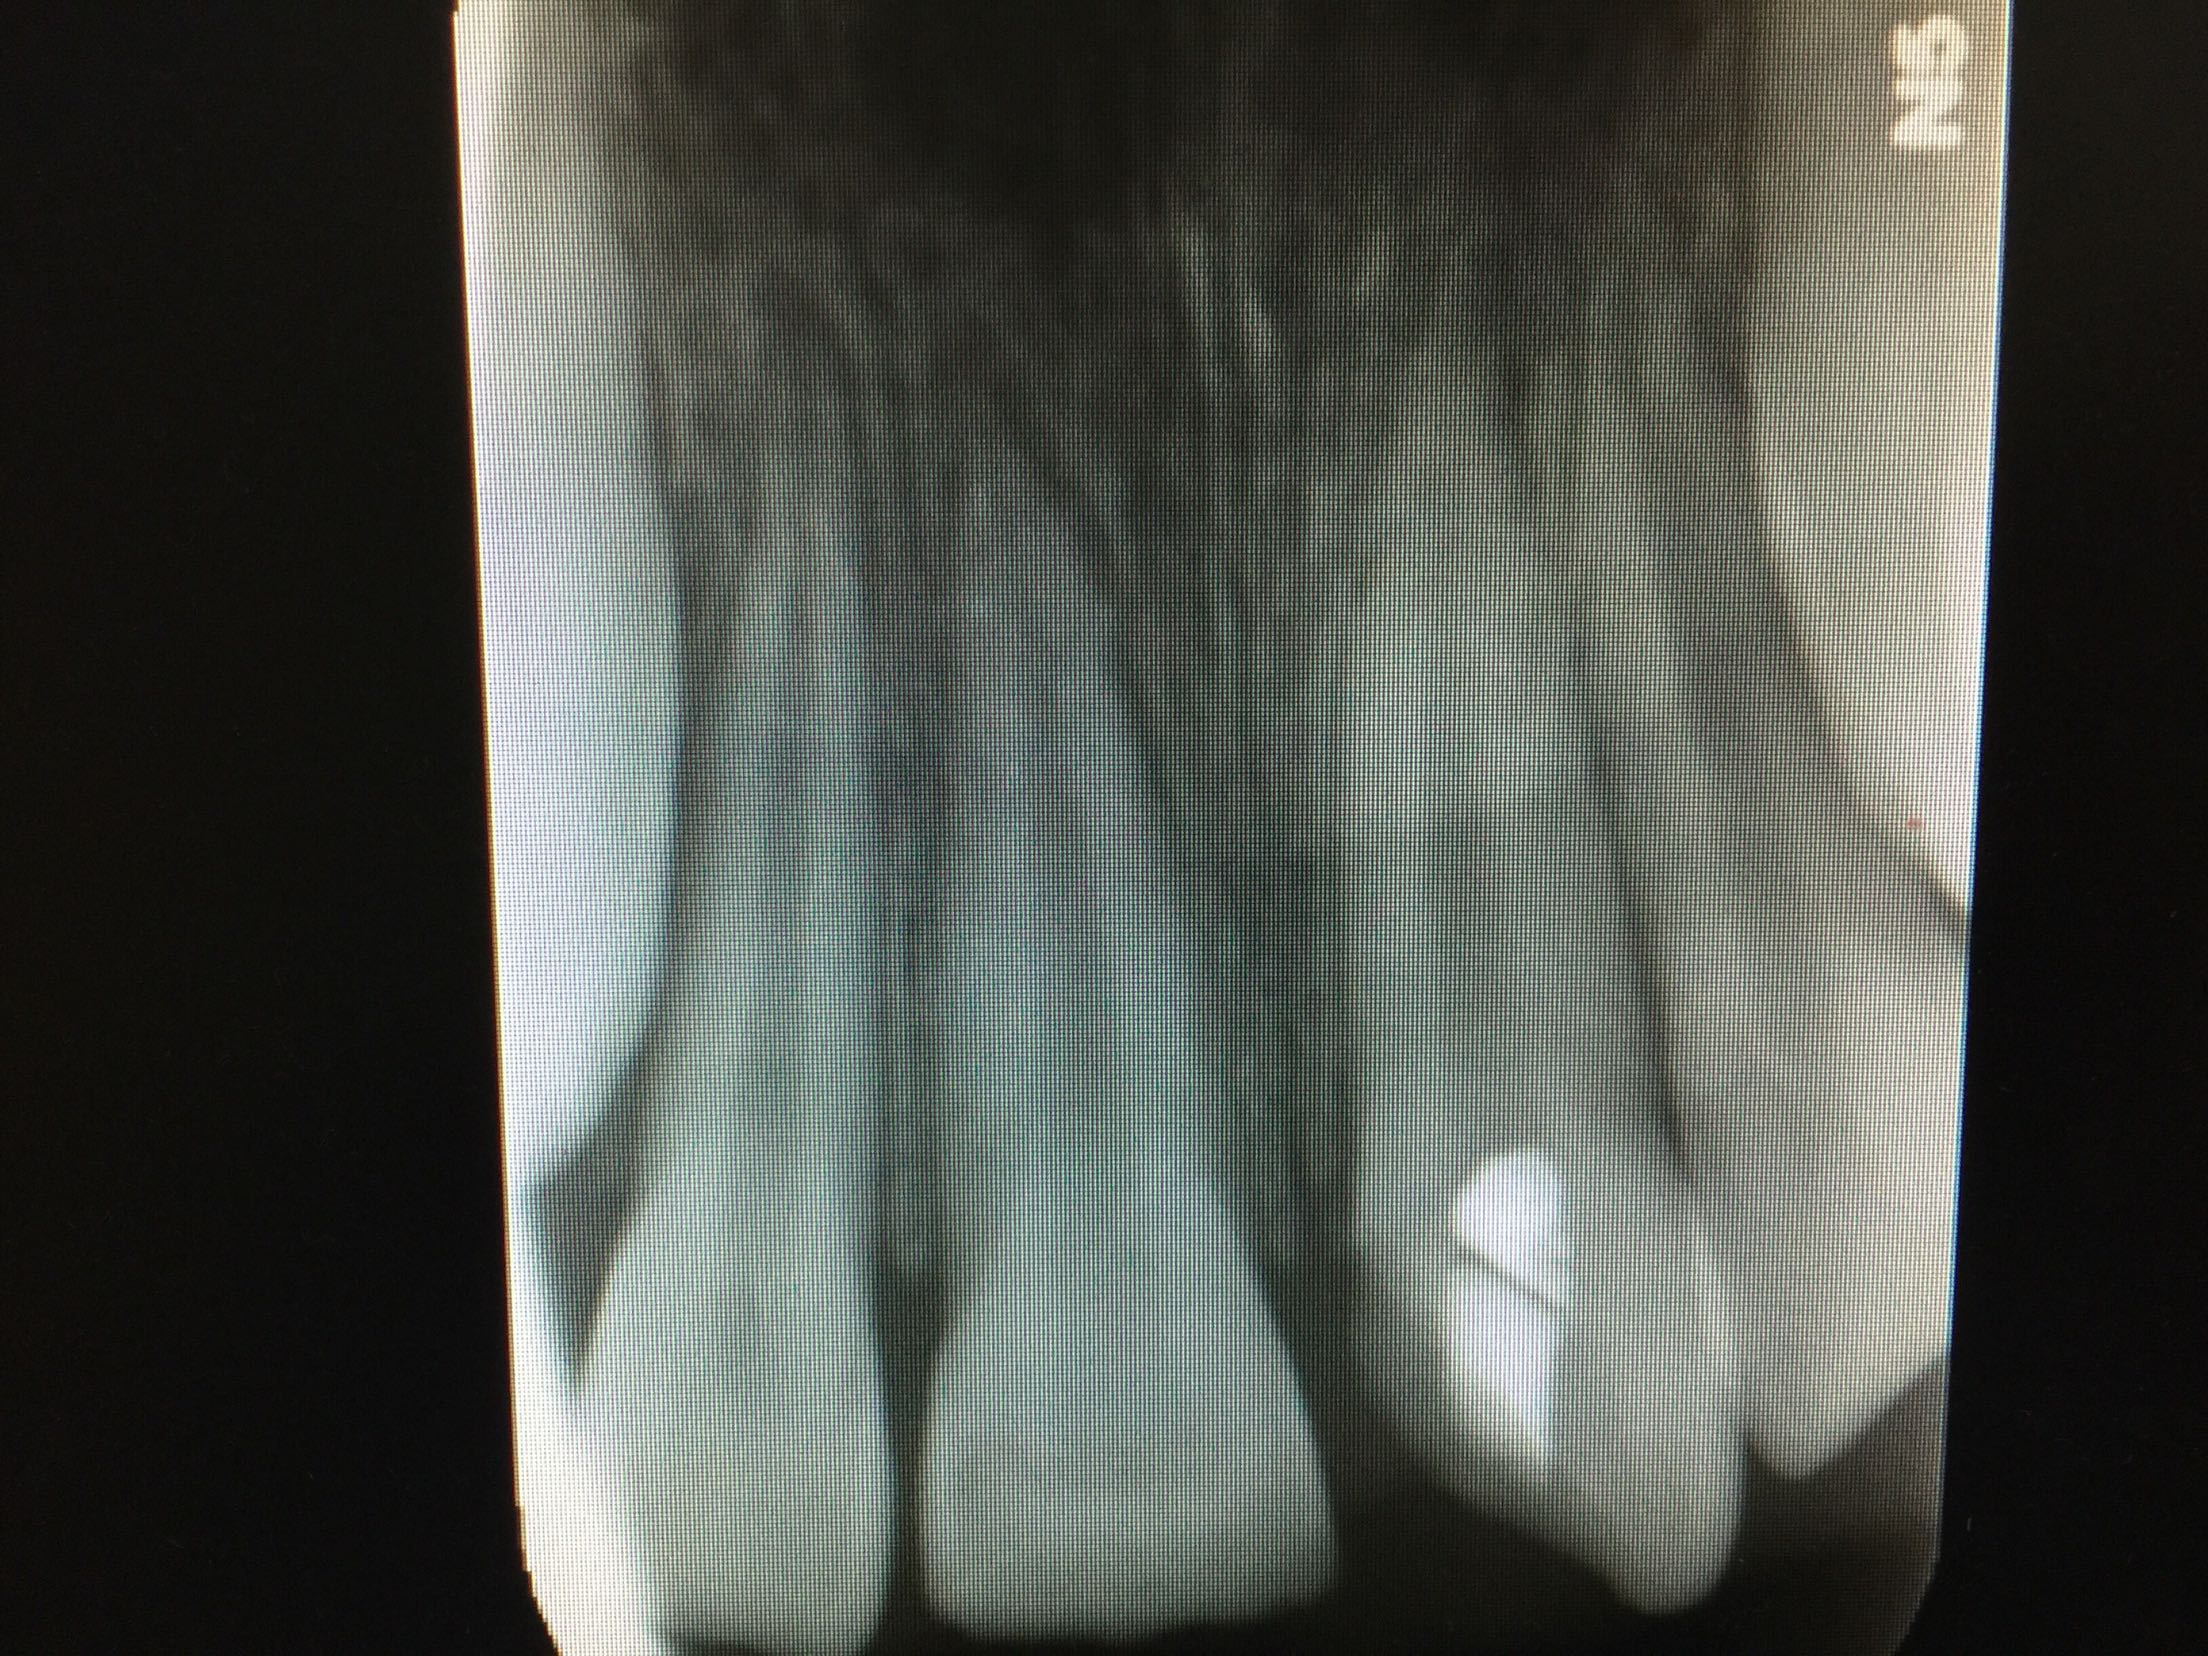

复诊,11,21牙进口玻璃离子垫底,前牙美容修复术调合,抛光。 3周后复诊:牙髓电活力测试11牙14,21牙15。 拍片:

11,21牙牙周膜腔未见明显增宽,很尖周无暗影。 建议继续拍片观察。 一月后复诊:牙髓电活力测试11牙13,21牙15。 拍片:11,21牙牙周膜腔未见明显增宽,很尖周无暗影。 建议11,21前牙树脂功能修复。 处置:行11牙,21牙牙树脂修复术。继续观察,约复诊。